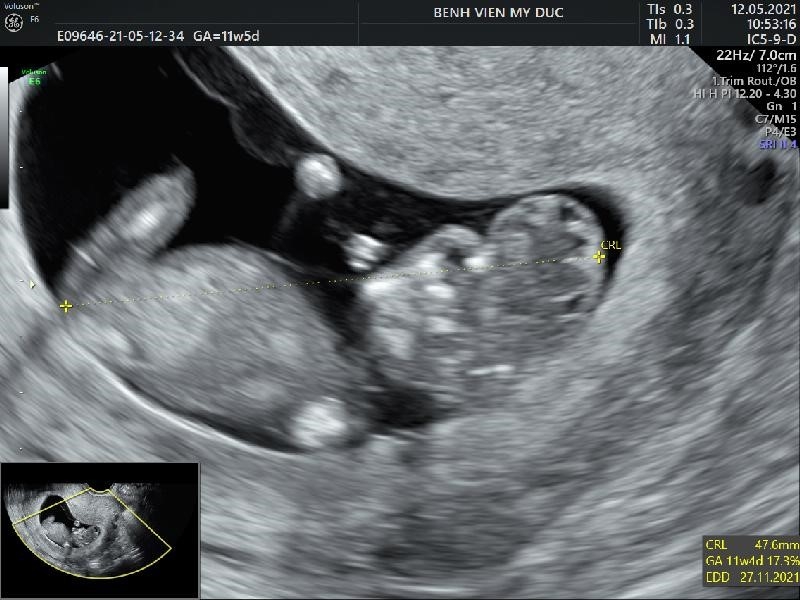

2.1.3. Some clinical cases:

![]() |

Brain parenchyma has no outer covering of the skull

Pregnancy stage 11-13, 6/7 weeks, the lateral ventricle is slightly large and is filled with 2/3 of the posterior horn by the choroid plexus. The two cerebral hemispheres are balanced and clearly separated by the sulcus and crescent of the brain. The corpus callosum is very thin, most clearly seen in the front, the ventricles are filled with fluid, so it should be distinguished from hydrocephalus. At this stage, some brain structures are not fully developed (such as the bottle, cerebellum) so they may not be visible.

Patient 13 weeks: first antenatal check-up found anencephaly